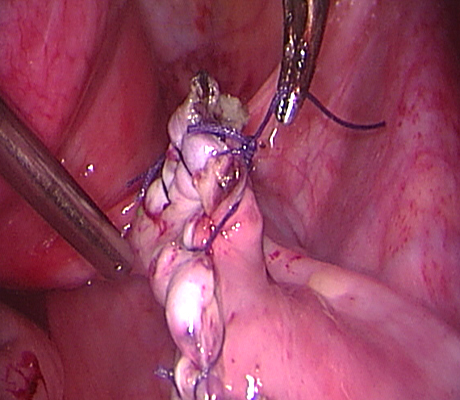

Examples of some pelvic masses dealt with by open surgery.

This is a big ovarian tumour (cancer) that was removed through open surgery.